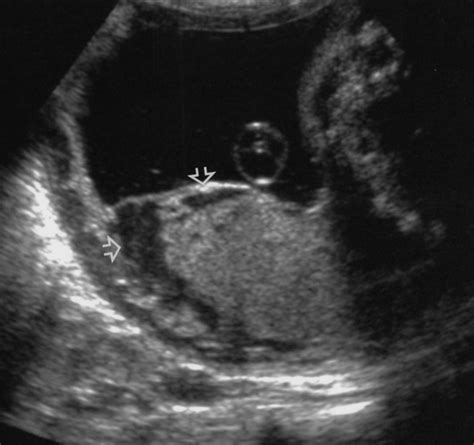

Diagnosing Placental Abruption

Diagnosing placental abruption can be challenging because the symptoms can be similar to other conditions. An ultrasound may be used to visualize the placenta and check for signs of separation. In some cases, a fetal heart rate monitor may be used to assess the baby’s well-being. Blood tests may also be ordered to check for signs of bleeding.

Placental abruption, also known as abruptio placentae, occurs when the placenta separates from the uterine wall before delivery. This can lead to severe bleeding and complications for both the mother and the baby. Placental abruption is less common than placenta previa, occurring in about 1 in 150 pregnancies.